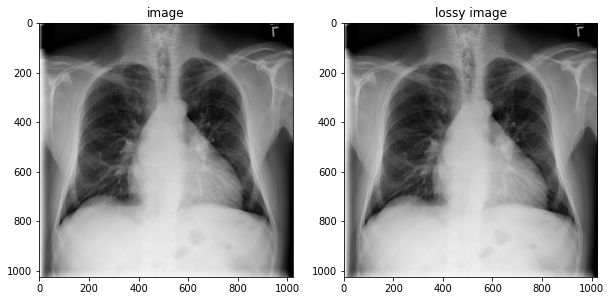

lossy_image = tfio.image.decode_dicom_image(image_bytes, scale='auto', on_error='lossy', dtype=tf.uint8)

fig, axes = plt.subplots(1,2, figsize=(10,10))

axes[0].imshow(np.squeeze(image.numpy()), cmap='gray')

axes[0].set_title('image')

axes[1].imshow(np.squeeze(lossy_image.numpy()), cmap='gray')

axes[1].set_title('lossy image');